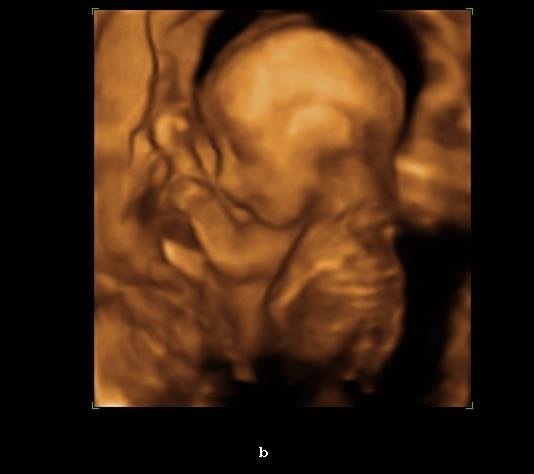

When I had my NT scan and A/S done they flipped on the 3d/4d for a little while to take a look, you could make out LO's face pretty decently at 21 weeks, so I'd say anytime after that and before things start getting cramped at around 30+ weeks should be good. I wouldn't worry about the safety part. There's no good evidence that ultrasounds pose any risk to unborn fetuses, and in many countries women are given routine ultrasounds at every visit and have no ill effects. Your doctor is just trying to cover their ass.

DD example -

Also I love the 3D because all my 2D look like alien babies and this one actually looks like a human baby